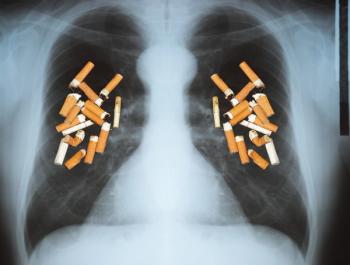

Undiagnosed lung disease in smokers, the impact of guidelines for community-acquired pneumonia in children, and climate change and asthma attacks make headlines in the respiratory news.